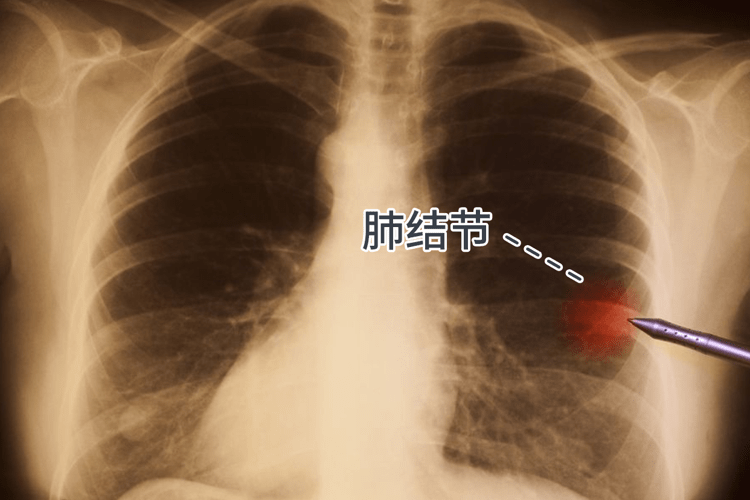

肺结节是指肺部内出现的直径,其中直径3cm的则被称之为肿块。结节的出现可能为单发也可能为多发,约有80%的肺结节性质为良性,不会给患者身体带来额外的影响。

厦门大学附属中山医院胸外科柯孙葵主任医师表示,肺结节≠肺癌,它只是影像学上的一个术语,并非疾病的诊断。肺结节患者出现肺癌的概率仅有3.7~5.5%,且这里面很大一部分患者有希望可以治愈。